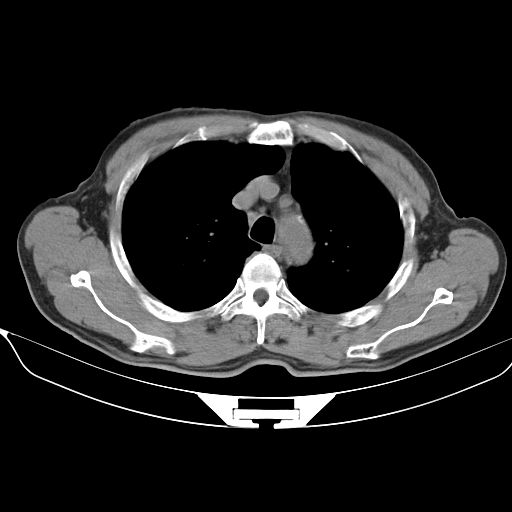

以下是引用心路寻觅在2010-3-1 10:23:00的发言:[br]1、考虑左肺上叶周围型肺癌[br]2、右上肺陈旧性病灶。[br][br][本贴已被 心路寻觅 于 2010-3-1 10:40:18 修改过]

以下是引用shuiyuan在2010-3-1 10:45:00的发言:[br]考虑左肺上叶中心型肺癌伴阻塞型炎症,邻近胸膜受侵。